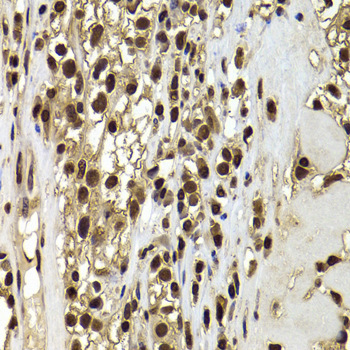

Immunohistochemistry of paraffin-embedded human kidney cancer using ACTL6B antibody at dilution of 1:100 (x400 lens).